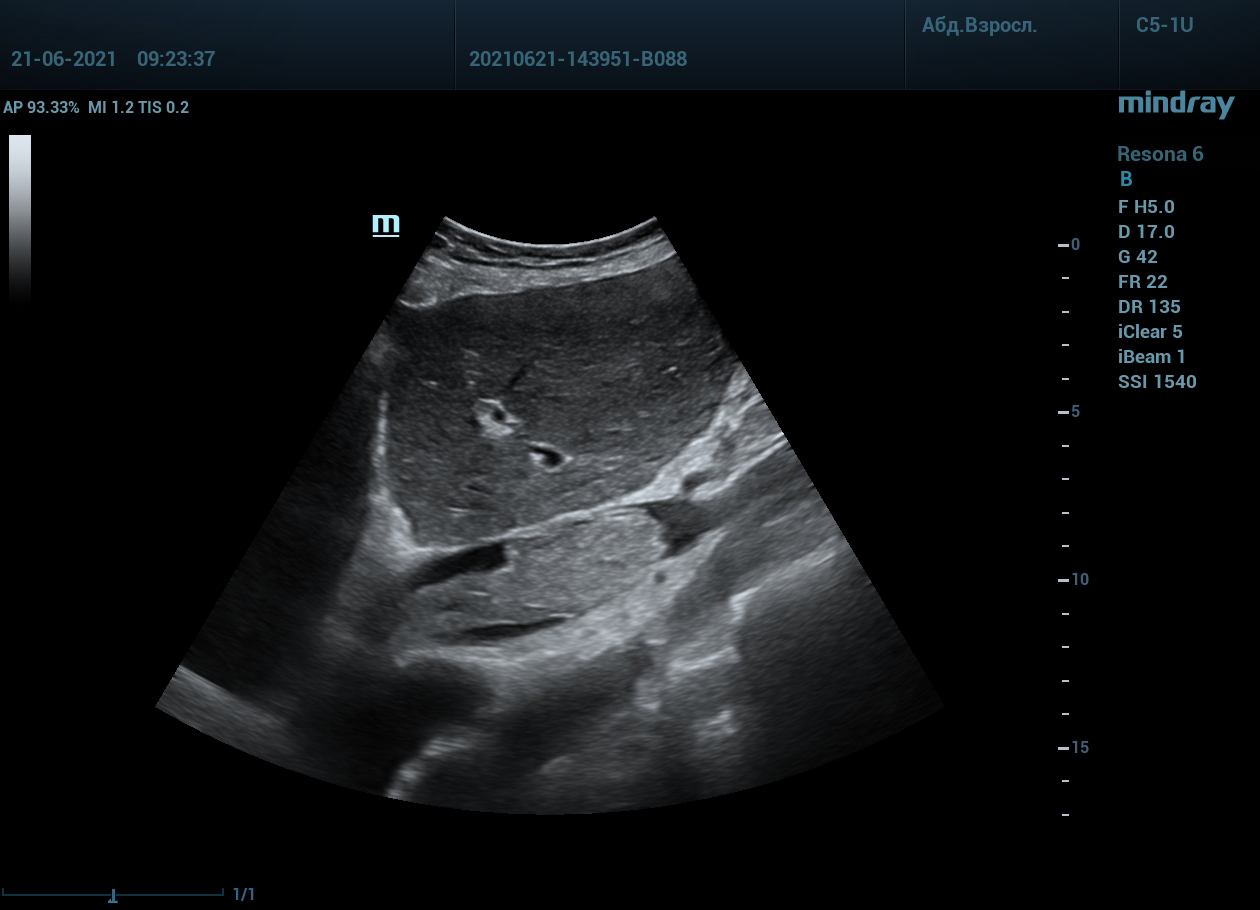

Интересный случай из практики нашего врача-аппликатора. Использовался экспертный ультразвуковой прибор Mindray Resona 6, стандартные заводские пресеты и автоматическая оптимизация iTouch. В эхокардиографии всегда помогает колорайзинг, чаще всего используется оранжевый оттенок. Пациент обследуется перед оперативным лечением по поводу онкологии почки. Вены нижних конечностей у данного пациента без особенностей, сжимаемы и проходимы. Казалось бы, проблема тромбоза миновала но в процессе эхокардиографического исследования, при сканировании нижней полой вены в субкостальном сечении, определяется эхогенное образование. Образование на месте просвета нижней полой вены. Вена расширена, эхогенное включение проникает в правое предсердие. По краю тромба в цветопотоковой визуализации определяется кровоток. Онкологическое заболевание почки осложнилось тромбозом почечной вены, с распространением тромба в нижнюю полую вену и правое предсердие. Изюминку добавляет то, что в других эхокардиографических сечениях тромб совершенно не виден.